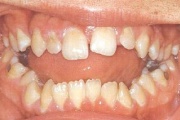

Puudub ülemine tsentraalne intsisiiv, kuid külgmised lõikehambad on juba lõikunud.

Puudub ülemine tsentraalne intsisiiv

Ruumipuudus eesmiste hammaste osas